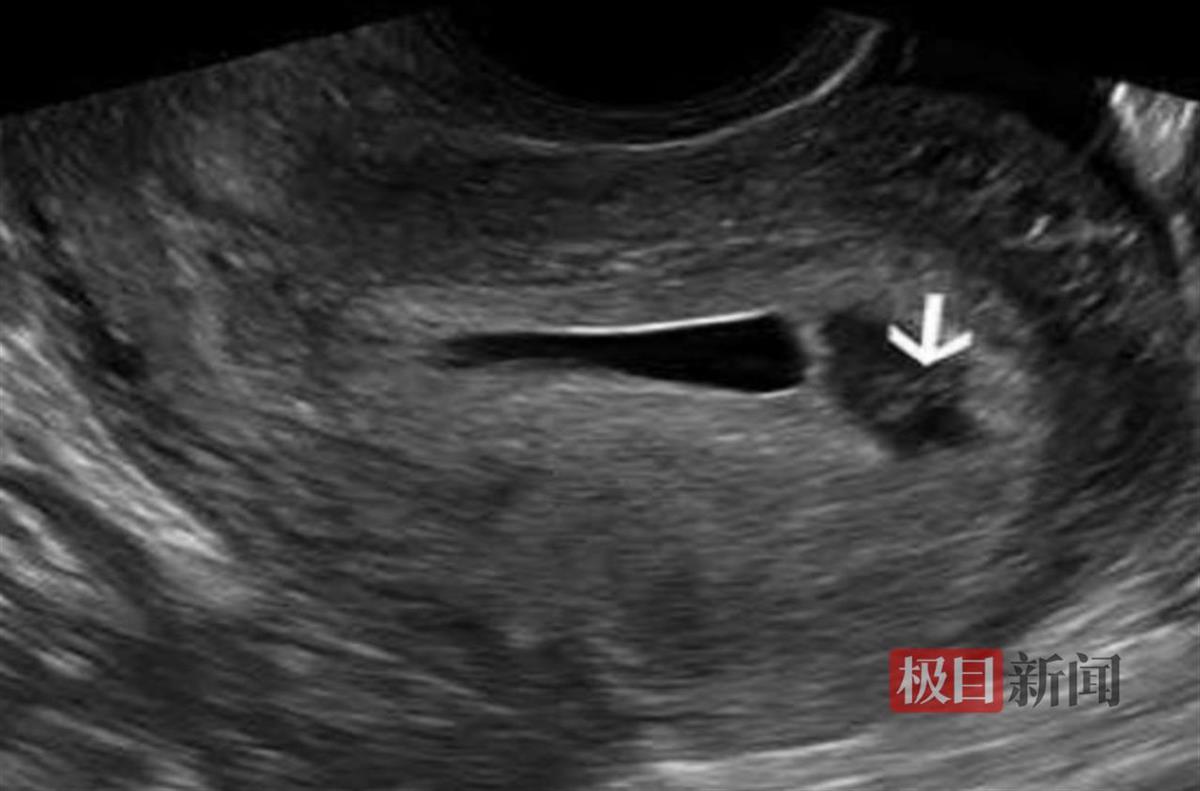

许女士今年38岁,怀孕后,很注意自己的孕期营养,如今她已怀孕12周左右,体重增加了不少,走路都有点喘气。她上网查询得知,可以通过做瑜伽来控制体重的增长,为此,许女士做起了瑜伽,刚开始运动了两天,她没看到什么效果,体重仍然增加得很快,于是许女士增加了训练强度。日前,她因为腹胀急诊,被送到武汉市汉口医院,妇产科医生会诊后表示,患者需要住院治疗。许女士当时还有些不解,觉得自己并没有撞到肚子,只是稍微有点腹胀,也没有出血,当天B超并没有发现什么异常情况,不知为何要住院治疗。不过为安全起见,她还是遵医嘱住院了。谁知,她住院1天后复查超声,发现绒毛膜下有约2.7厘米×1.4厘米的血肿,被诊断为绒毛膜下血肿、先兆流产。经保胎治疗2周后,许女士平安出院。

检查影像图(通讯员供图)

该院妇产科副主任赵枫介绍,绒毛膜下血肿,又称为胎膜后出血或绒毛膜下出血,是指妊娠期间在胎盘与子宫壁之间形成的血液聚集。这种情况通常发生在妊娠早期和中期,血液积聚在绒毛膜(胎盘的主要组织之一,位于胎盘和子宫之间)与底蜕膜之间,形成血肿。每年急诊妇产科都会接诊很多类似许女士这样的孕妇,因为运动过量,出现不适来就医,表面上并没有发生腹部磕碰、腹部疼痛和出血症状,但经过48-72小时观察后,一部分出现了先兆流产症状,及时发现与治疗后,预后都很好。